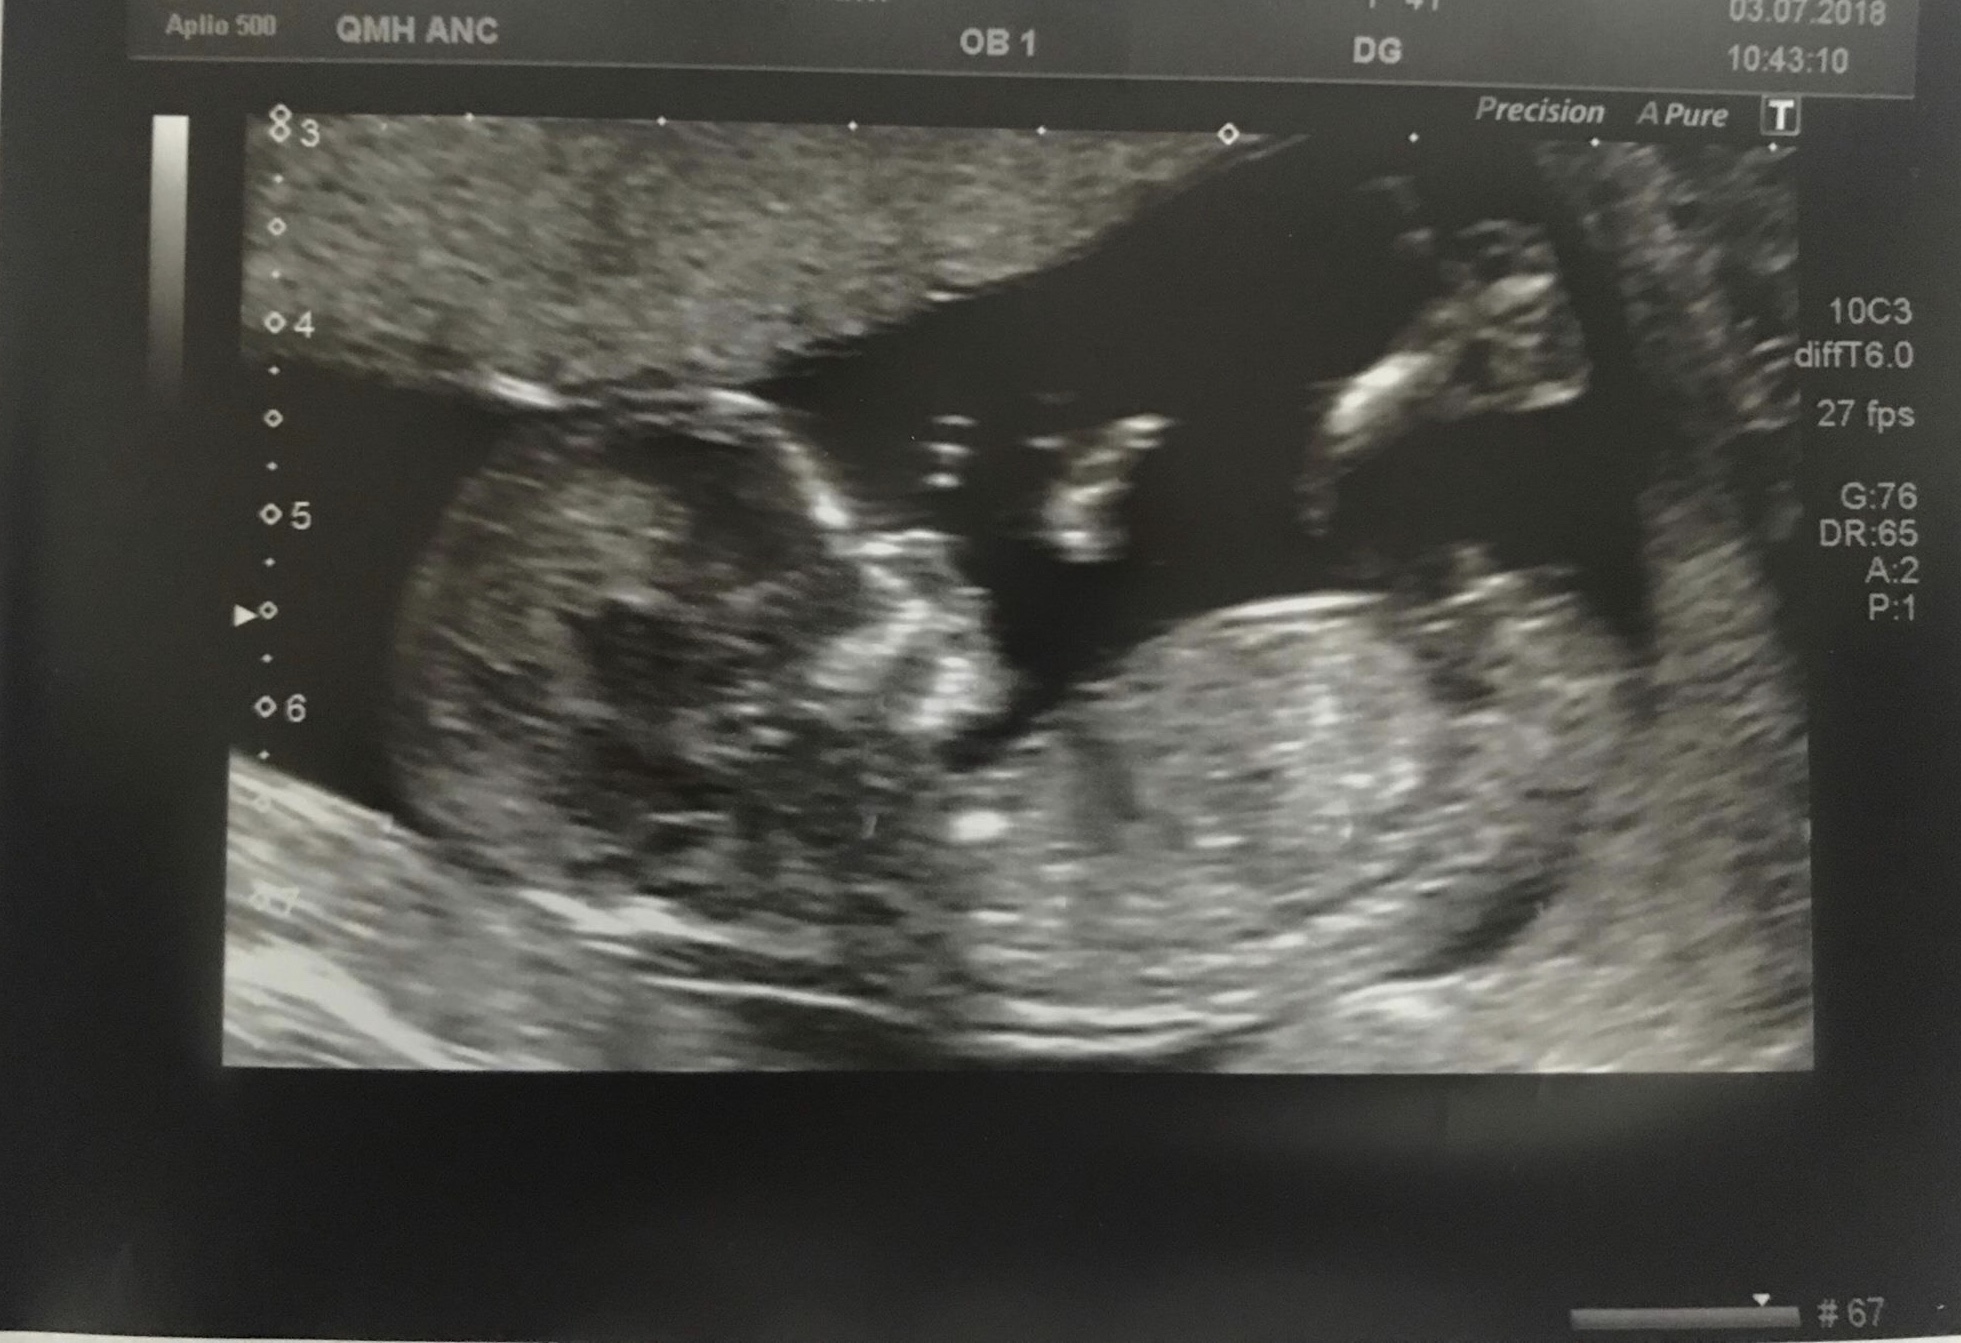

Attachment 39921Hi this is our 13 week exactly scan pic.

Do you think boy or girl??

The nub isn't the clearest but leaning boy.